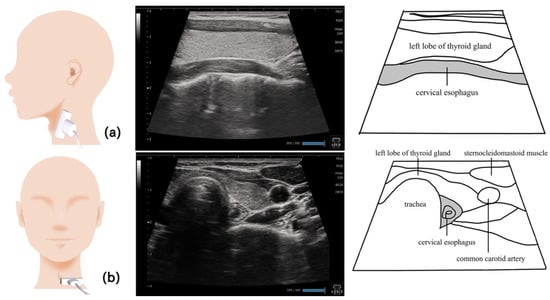

12. Esophagus (Figure 12)

- Moriniere, S.; Hammoudi, K.; Marmouset, F.; Bakhos, D.; Beutter, P.; Patat, F. Ultrasound analysis of the upper esophageal sphincter during swallowing in the healthy subject. Eur. Ann. Otorhinolaryngol. Head Neck Dis. 2013, 130, 321–325. [Google Scholar] [CrossRef] [PubMed]

- Watanabe, M.; Hironaka, S.; Utsumi, A.; Murata, N.; Mukai, Y. The standardized method for ultrasound imaging of oropharyngeal on swallowing. J. Jpn. Soc. Disabil. Oral. Health 2011, 32, 19–28. (In Japanese) [Google Scholar]